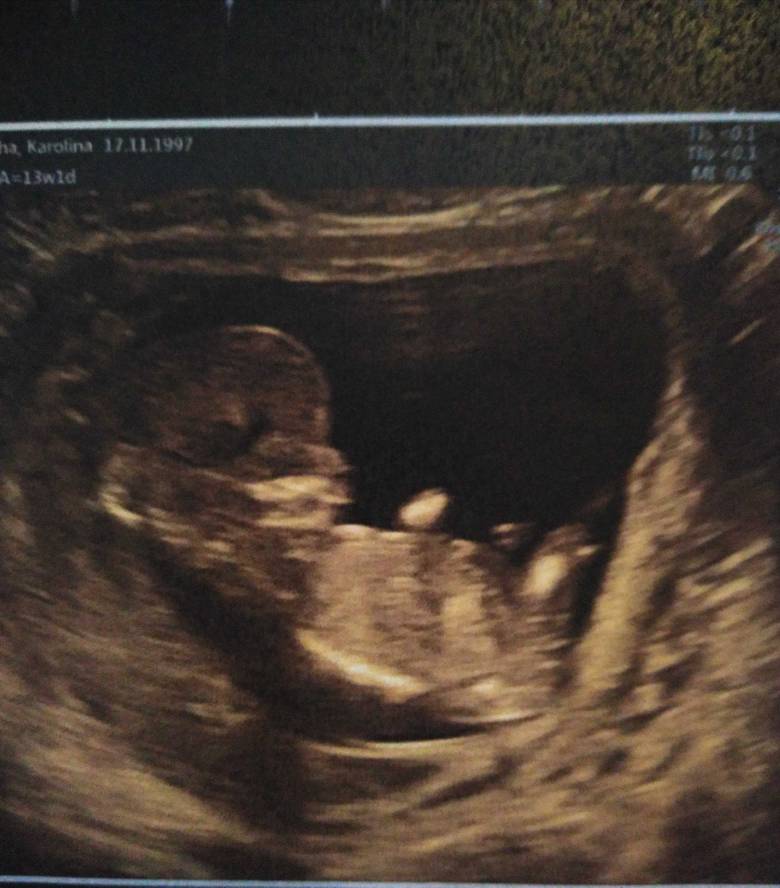

Witajcie [emoji4] Wczoraj nic nie pisałam już bo byłam padnięta po nocy i stwierdziłam, że dzisiaj napisze jak po usg. Wykluczone wady genetyczne, ciąża o 6 dni starsza, serduszko ślicznie biło [emoji7] przeziernosc karku 1,9 wszytko było ładnie widać kość nosowa, nóżki, rączki itd. Mąż był wzruszony tym bardziej jak widział, że dzisiaj pięknie się rusza i łapie po główce [emoji4] Jak spytałam się o płeć to powiedziała pani doktor, że troszkę za wcześnie na to ale z wyrostka plciowego wychodzi dziewczynka [emoji3590] Nie jest to pewne ale oboje z mężem tak czujemy, że dziewczynka [emoji7] Dodaje kilka zdjęć może wy również potwierdzicie [emoji4]

Witajcie [emoji4] Wczoraj nic nie pisałam już bo byłam padnięta po nocy i stwierdziłam, że dzisiaj napisze jak po usg. Wykluczone wady genetyczne, ciąża o 6 dni starsza, serduszko ślicznie biło [emoji7] przeziernosc karku 1,9 wszytko było ładnie widać kość nosowa, nóżki, rączki itd. Mąż był wzruszony tym bardziej jak widział, że dzisiaj pięknie się rusza i łapie po główce [emoji4] Jak spytałam się o płeć to powiedziała pani doktor, że troszkę za wcześnie na to ale z wyrostka plciowego wychodzi dziewczynka [emoji3590] Nie jest to pewne ale oboje z mężem tak czujemy, że dziewczynka [emoji7] Dodaje kilka zdjęć może wy również potwierdzicie [emoji4]Zobacz załącznik 924495Zobacz załącznik 924497